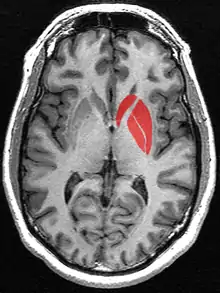

![]() Tractography showing corticostriatal connections | |

Striatum highlighted in green on coronal T1 MRI images

Striatum highlighted in green on sagittal T1 MRI images

Striatum highlighted in green on transversal T1 MRI images